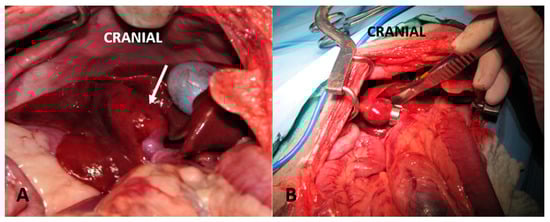

3.2. Gradual Attenuation